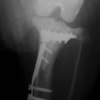

術後写真

手術前後のTPA(脛骨高平部の角度)を測定しています。

約29°から約10°へ矯正されています。

本症例は、走った後に左後肢を挙上していることを主訴に来院されました。触診時に左膝関節のクリック音を聴取、レントゲン検査にて左脛骨の前方変位が認められました。術中に、前十字靱帯の断裂及び内側半月板の損傷、内側の軟部組織の顕著な腫脹を確認。半月板切除、TPLOを実施しました。周囲組織への炎症の波及もあったため回復に時間を要しておりますが、徐々に跛行頻度は減少傾向にあり、現在も経過観察中です。術前に約29°あったTPAは術後に約10°まで矯正されました。